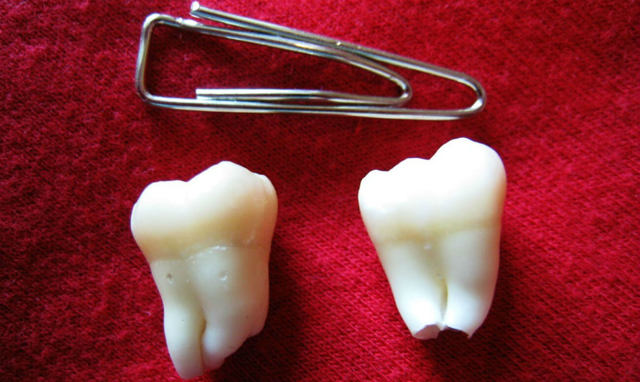

Внешне зуб мудрости практически ничем не отличается от остальных моляров. Он имеет такой же размер и форму, но определенные отличия все же имеются. Восьмерки почти всегда располагаются под небольшим наклоном, что объясняется узостью челюстной дуги и отсутствием места для нормального роста.

В отличие от первого и второго моляров, на поверхности зуба мудрости отсутствуют фиссуры – небольшие углубления в виде ямок и бороздок, возникающие в результате частого жевания и перетирания пищи.

Это связано с тем, что последние моляры практически не испытывают жевательной нагрузки из-за своего расположения и их поверхность дольше сохраняет свою гладкость.

Главным отличием зубов мудрости от премоляров и моляров является сложная корневая система. Корни восьмерок обычно больше и длиннее, чем у остальных зубов, и всегда растут под наклоном, часто переплетаясь между собой.

Третьи моляры относятся к многокорневым зубам и обычно имеют от трех до пяти корней. При раннем прорезывании некоторые корни могут остаться недоразвитыми – увидеть это можно только на рентгеновском снимке, который рекомендуется всем после прорезывания восьмерок, чтобы изучить их строение и оценить возможные риски в будущем.

Строение зуба мудрости ничем не отличается от структуры других моляров: шейка, корневая система (4–5 штук), коронка. При нарушении развития корни могут образовывать единый конгломерат – вырастает однокорневой зуб.

- Большее, по сравнению с другими молярами, количество корней: до 5 штук. От того, сколько корней имеется у зуба мудрости, часто зависит проблематичность его лечения или удаления.

- Корни восьмерок значительно изогнуты, что создает трудности при чистке, лечении каналов.